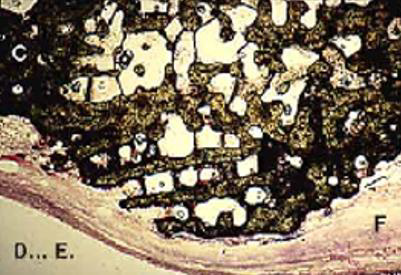

The coral purification was obtained down to the aragonite crystal using super-critical fluids according to the technique developed by Professor Le Petitcorps see Figures 5&6.

Role of Vascularization

In necrotic bone or in bone in contact with inert metallic material (such as a plate, screw, nail), there is no possibility of developing adequate vascularity. The (Figure 7) shows as an example that there is no modification of the biomaterial of the coral Porites spheres in contact with the inert metallic biomaterial. In fact, the biomaterial remains in the mineral state, surrounded by an avascular fibrous sleeve. This supports the argument that vascularization has a fundamental role. On the contrary, adjoining the well-vascularized cancellous bone, the biomaterial is integrated and assimilated by a double mechanism: demineralization process with the osteoclast’s activities, then remineralization process with the osteoblast’s actions, and a newly formed bone appear as shown in Figure 8.

Figure 7: The natural coral Porites spheres in contact with inert metallic material have remained intact. They were surrounded by fibrous tissue without vessels. (Magnification 0,35 x 1,35).

Figure 8: The coral spheres in contact with the bone and the vessels that run through it have been colonized by bone cells which have undertaken the resorption of the biomaterial. (Biomatech laboratory) (Magnification 0,35 x 1,35).